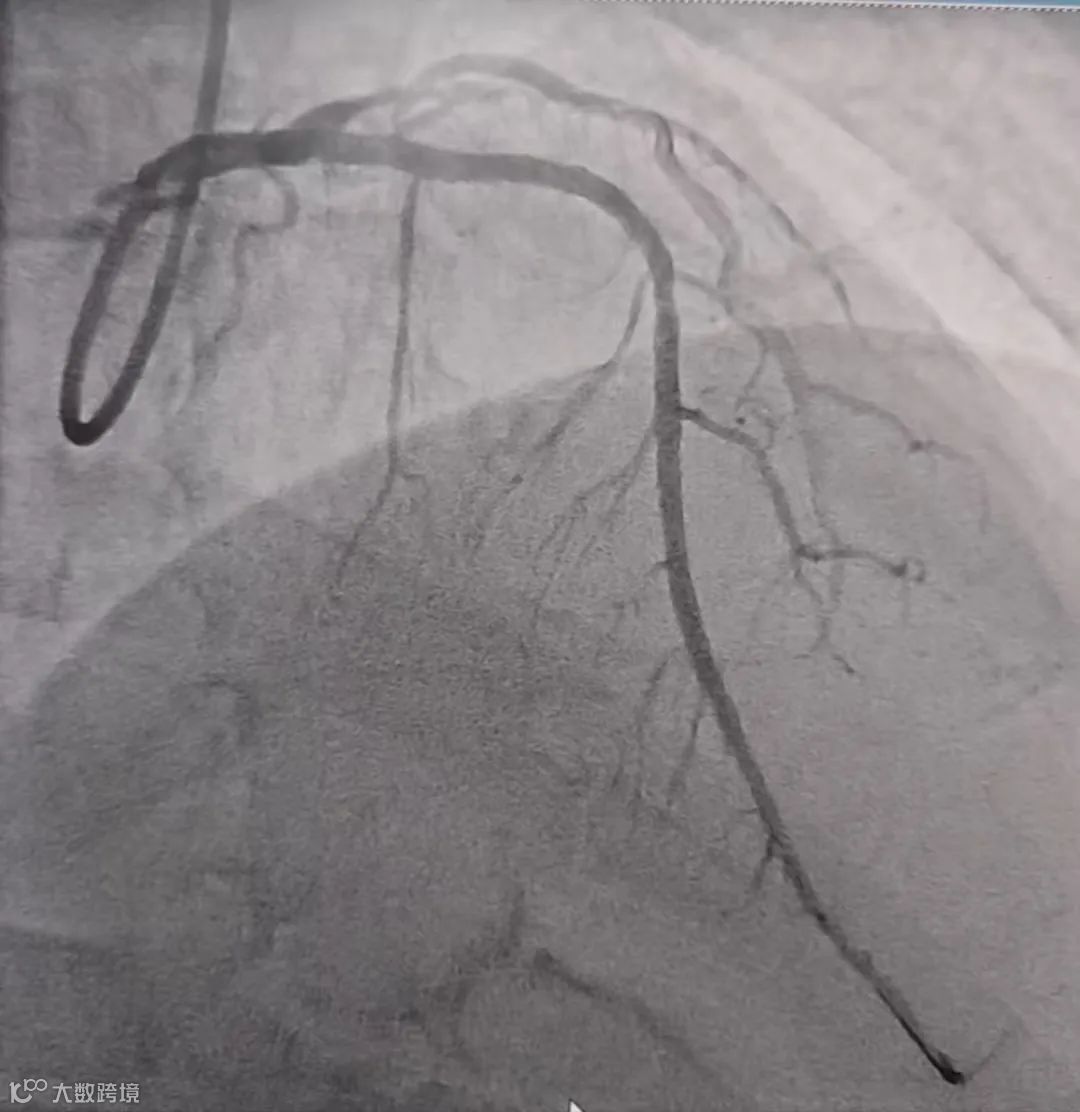

(球囊扩张与溶栓后血管通畅)